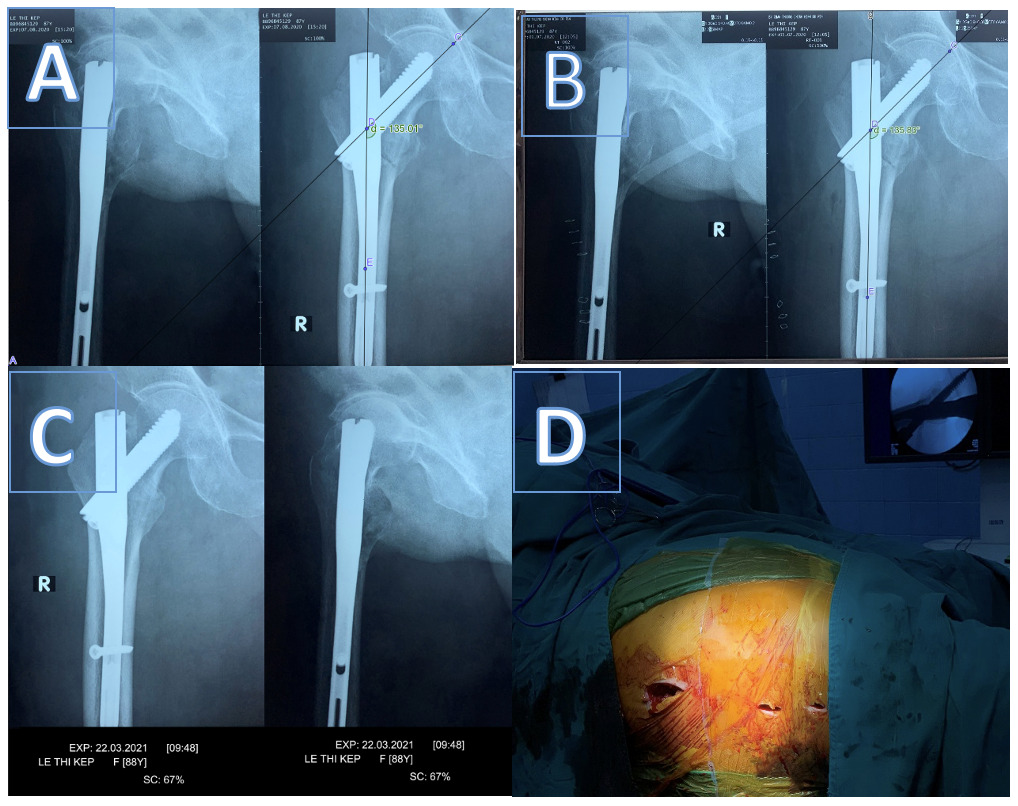

Recovery of neck-shaft angle immediately post-surgery compared to the unaffected side: 9 cases had their neck-shaft angle restored to that of the unaffected side (25.7%), 5 cases had a larger neck-shaft angle post-surgery (14.3%), and 21 cases had a smaller neck-shaft angle post-surgery, ranging from 1 to 15 degrees smaller than the unaffected side (40%).

Change in neck-shaft angle at the final assessment compared to immediately post-surgery: nearly 70% of cases showed no change in the neck-shaft angle of the femur six months after surgery, while 30% exhibited a decrease (varus deformity), with the majority experiencing a decrease of 1 – 5 degrees (22.86%).